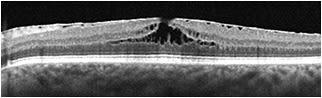

With careful clinical observation, most of the entities above can be accurately identified prior to ancillary testing. In practice, the most common entity that falls under the label of MPH is an ERM with invaginated foveal tissue (Figure 2). The OCT findings with this subtype of ERM include2 invaginated or heaped foveal edges, concomitant ERM with central opening, steep macular contour to the central fovea with near-normal central foveal thickness, and no loss of retinal tissue.

Figure 2. OCT of ERM with invaginated foveal tissue. Clinically, the eye would be in the category of macular pseudohole. Note that all retinal layers are intact.